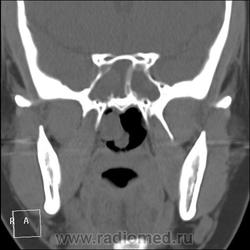

КТ ППН и носоглотки. Девушка 21 года. Полипозный риносинусит.

Госпитализирована для оперативного лечения. Удалены полипы носа. Вторым этапом планируется гайморотомия. Во время операции - подозрение на образование носоглотки. Сохраняется затруднение носового дыхания. Направлена на КТ. Категорически отказалась от контрастировния (лекарственная полиаллергия, боится).

Полип в носоглотке справа. Нарушена пневматизация придаточных пазух носа кроме левой решётчатой. В левой гайморовой на дне неясно что…

На дне гайморовой - полип, в носоглотке немаленький хоанальный полип. Там всё в полипах, а они и фиброзные бывают, и ангиофибромы, и ангиоаденомы... Вот и плотность разная.

Ну, как-то все в одну кучу - и полипы, и ангиофибромы. При ангиофиброме, например, околоносовые пазухи свободны. А гиперденсность более характерна для грибкового поражения (аспергилеза), в том числе и "севшим" на пломбировочный материал.

На операции визуально полипы аденоматозного типа. Какие будут гистологически после гайморотомии - сейчас трудно сказать. Если б гиперденсность была только по нижней стенке верхнечелюстной пазухи, тогда вариант с аспергиллезом на пломбировочном материале, на мой взгляд, был бы более вероятен. У девушки участки гиперденсности по всем стенкам верхнечелюстных пазух, в основной пазухе, совсем чуть - в решетчатом лабиринте слева, без костной деструкции. Без посева и гистологии - только гадать)). В носовой полости признаков грибкового поражения ЛОРы не отмечают. Но Вы правы, может иметь место изолированное поражение синусов.